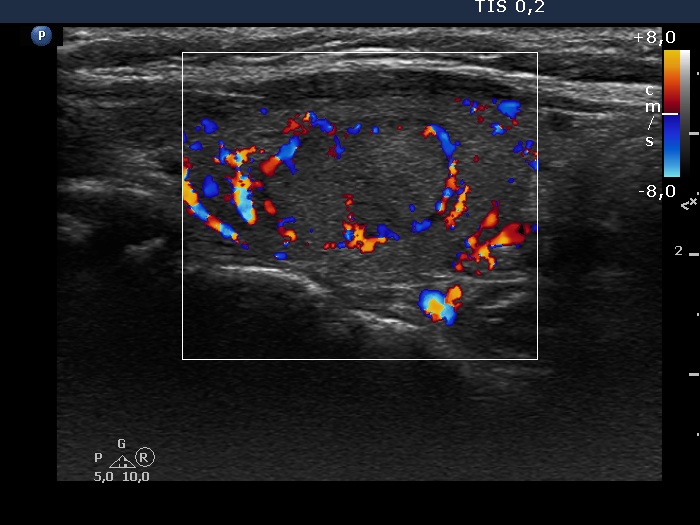

Discrete lesion or nodule in Hashimoto's thyroiditis - case 18 (99) (ultrasonographic picture 8)

Left lobe, longitudinal scan, color Doppler mode.